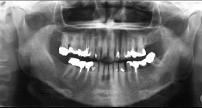

- 单项选择题黏液表皮样癌(如组图)以下哪种说法不正确 ( )

A、多发生在腮腺

B、一般分为高分化和低分化两类

C、高分化者少见颈淋巴结转移

D、低分化者常见颈淋巴转移

E、各型治疗原则相同